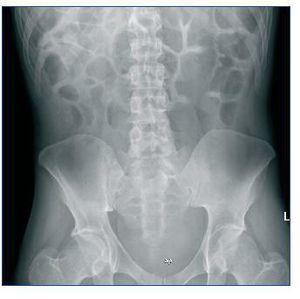

Dear Editor, Colonoscopy preparation solutions are widely used due to their rare side effects. However, we must exercise caution when using them in extremely old or young patients and those with digestive and/or renal diseases.1 In patients with renal failure, it may trigger severe electrolyte imbalances, including severe hypernatraemia, hyperphosphataemia, hypokalaemia, metabolic acidosis or renal failure secondary to dehydration. We herein describe a case with those alterations and severe clinical consequences. Male patient aged 30 years with a history of congenital encephalopathy and secondary mental retardation, congenital digestive disorder, chronic renal polycystic changes with severe long-term ureterohydronephrosis and secondary chronic renal failure with recurring urinary tract infections. The patient is a dependent for all life activities. He was admitted due to a partial ileus (figure 1) secondary to foreign objects (plastics, soil, etc.), with unremarkable blood chemistry except for a serum creatinine (Cr) level of 1.4mg/dl that he already presented in previous laboratory tests. From the time he was admitted, he was treated with abundant fluid therapy and cleansing enemas, and various types of foreign bodies were obtained over the following three days. On the fourth day after admission his state of consciousness began to deteriorate progressively and the blood test showed the following: Cr, 5mg/dl; urea, 116mg/dl; Na, 197mmol/l; K, 2.6mmol/l; Cl, 159mmol/l; pH, 7.2; HCO3, 14.9mmol/l; GAP, 23; Ca, 7.4mg/dl; P, 14.9mg/dl, and osmolarity 389mOs/kg. Given data indicating renal failure, normochloraemic metabolic acidosis, hypernatraemia, hypokalaemia and hyperphosphataemia, and their severe clinical repercussions, we decided to perform a session of haemodialysis, and the patient responded well. After two additional haemodialysis sessions we obtained electrolyte levels within the normal range and resolution of the neurological syndrome that had occurred. When the patient was discharged from the hospital, nitrogen retention levels had been stabilised and were similar to those at time of admission. Due to the low clinical suspicion of this condition, diagnosis and initiation of treatment are often delayed, and for that reason, mortality is between 17 and 33% depending on the series.2 To conclude, we must evaluate the risk-benefit continuum before using a colonoscopy preparation and if it is necessary, use preparations specially designed for patients with renal failure, such as XPrep.3,4

Figure 1. Simple radiography of patient's abdomen at admission.